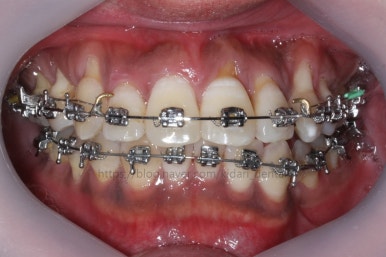

치료 시작 3개월째의 모습입니다.

서서히 가지런해지는 느낌이 드시나요?

화살표를 보면 작은 어금니 하나가 아래로 꺼져있는데, 이 녀석 때문에 애를 먹었네요. 훨씬 치료가 빨리 끝날 수 있었는데 이 치아가 워낙 잘 안움직이는 바람에 2년 개월정도로 치료기간이 많이 걸린 편이었어요.

치료 8개월째의 모습입니다.

이제 얼핏 보면 매우 가지런해졌어요. 이 뽑은 자리도 많이 남지 않았고 왼쪽 위 송곳니가 없지만 그리 표시도 많이 나지 않네요.

대신 위쪽 아래 작은 어금니가 애를 먹이고 있어요. 낚시줄처럼 부여매고 끌어올리는게 보이실거에요.